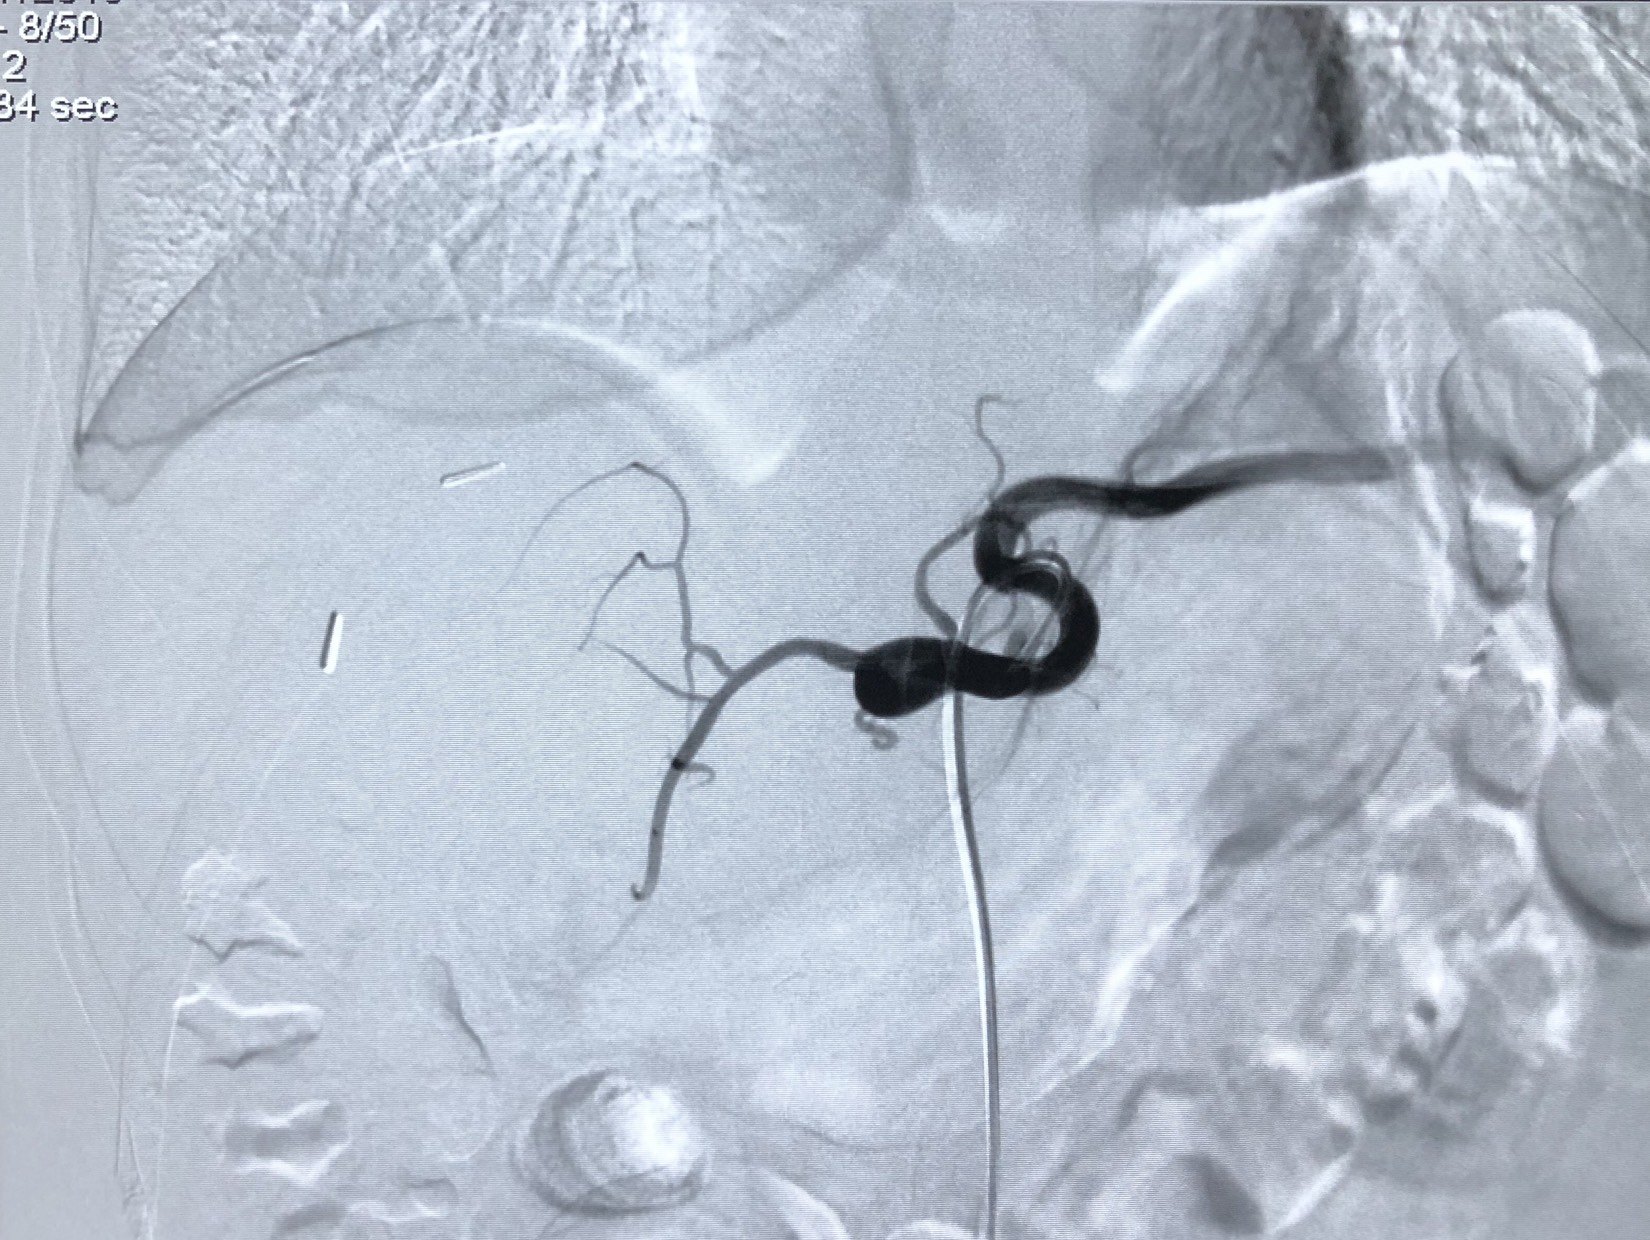

肝动脉造影可见浅淡染色